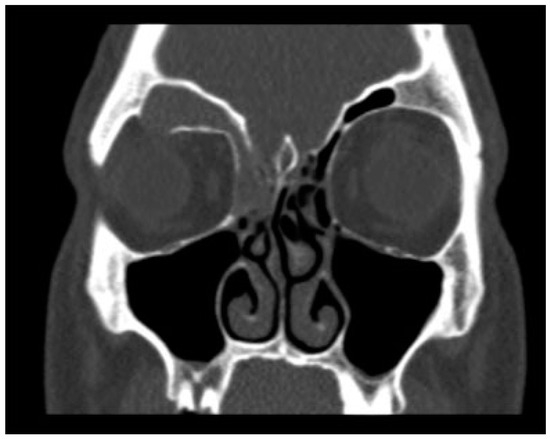

Figure 6. CT in the coronal plane demonstrating a right frontal sinus mucocele. The right frontal sinus is completely opacified with associated bony resorption at the superior orbit.